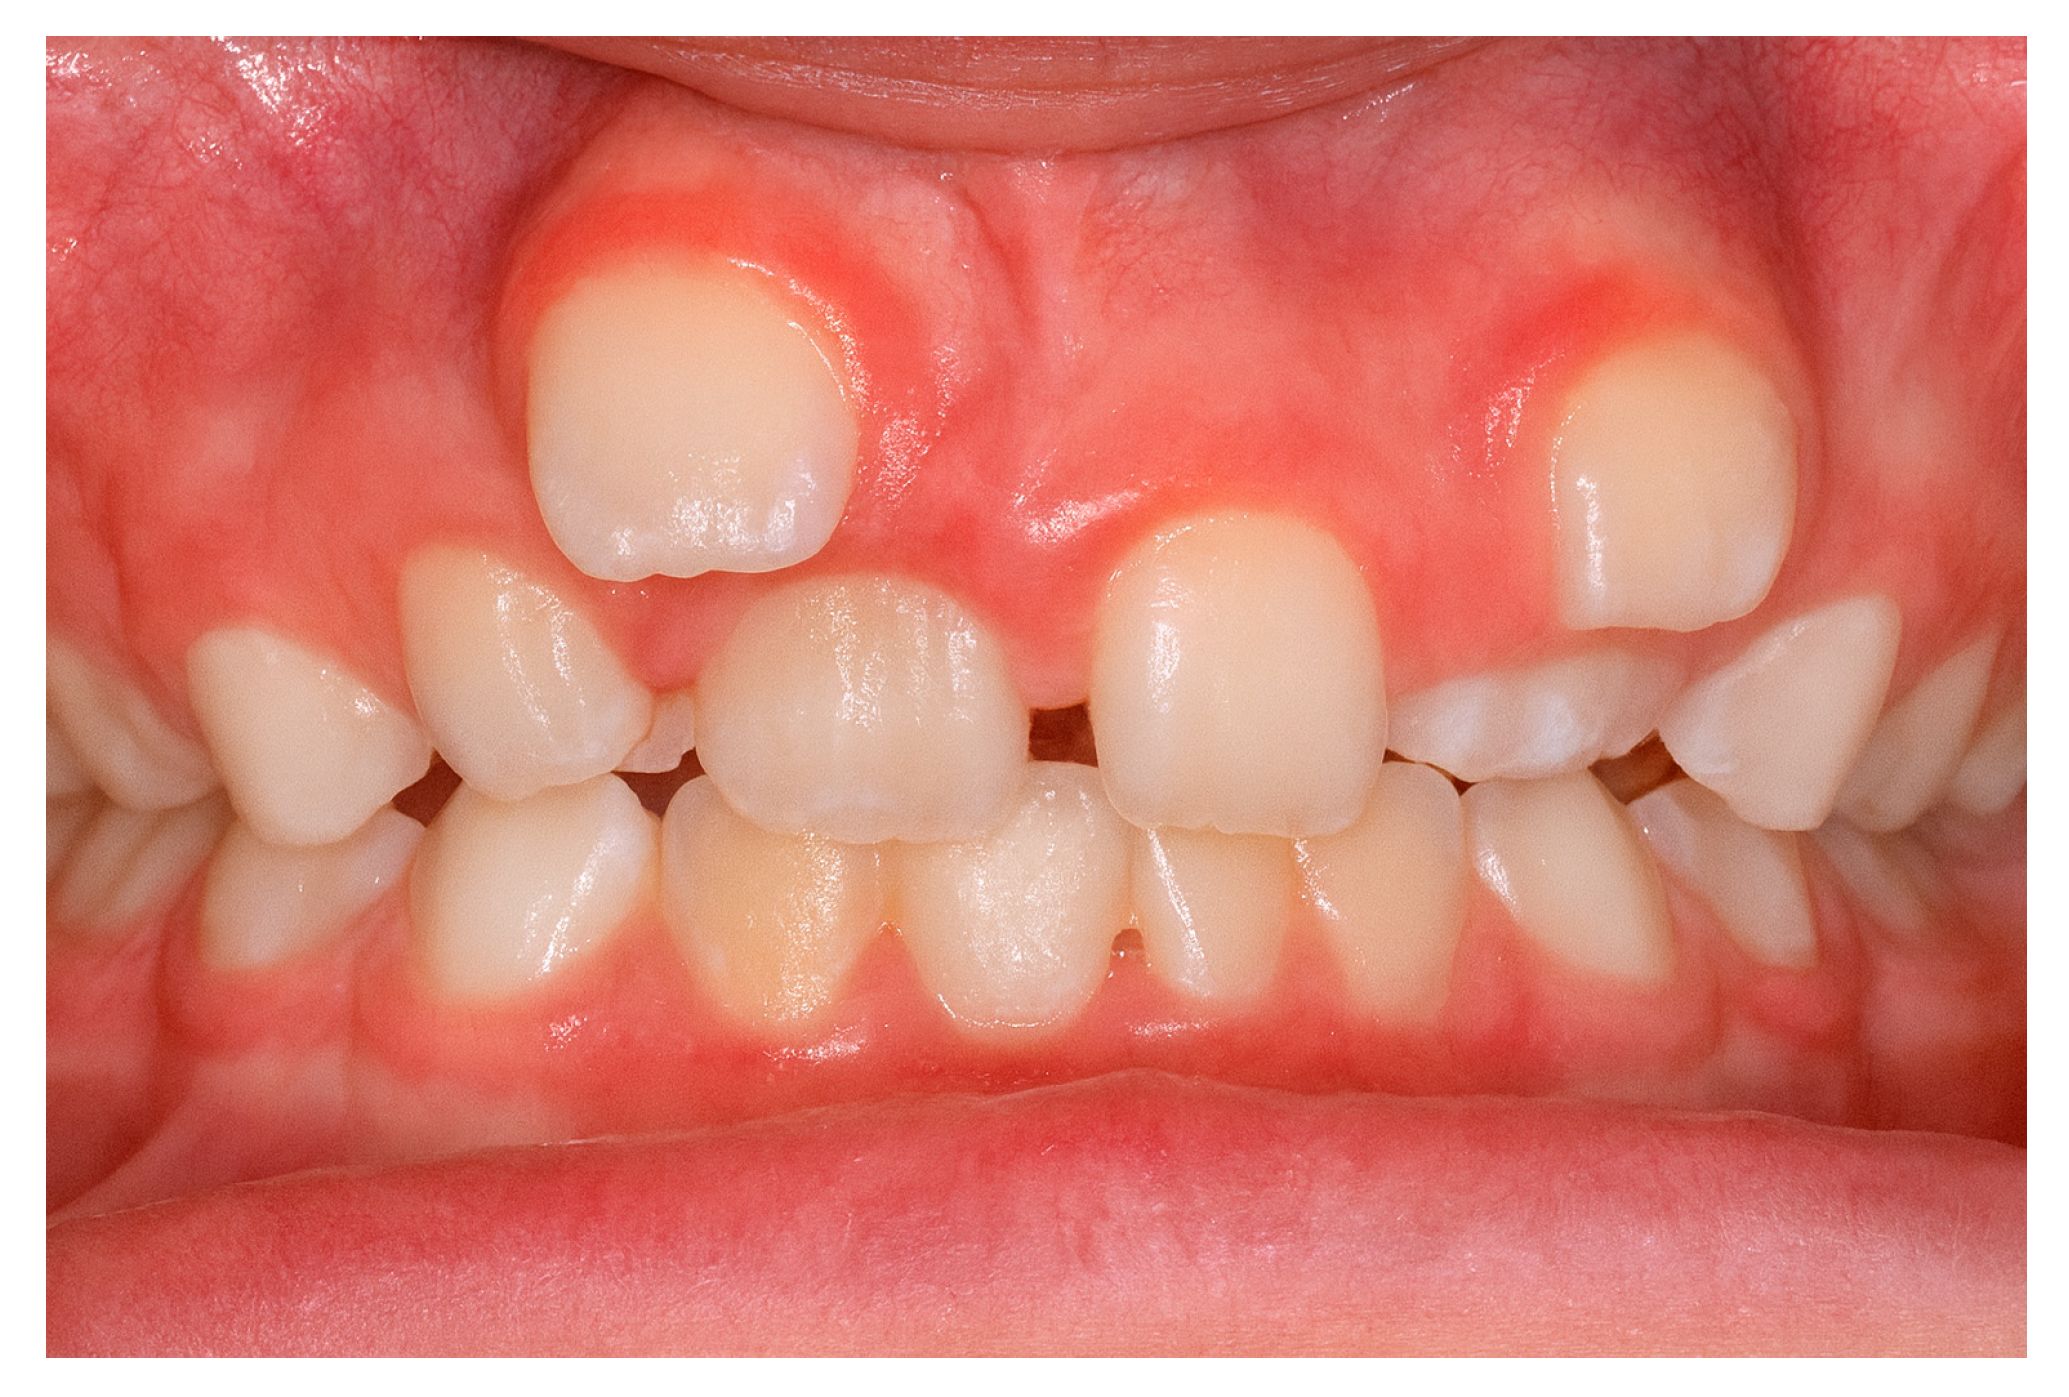

The increased frequency of ST in the maxillary incisor region (Figure 2) may be linked to intricate tissue rearrangements and morphogenetic activity in this area [2,17,20,25]. Nevertheless, no single theory fully accounts for the wide diversity of clinical presentations, suggesting that the etiology of ST is multifactorial, shaped by a complex interplay between genetic predisposition and environmental influences [3,24].

Figure 2. Supernumerary teeth located in the maxillary incisor area.